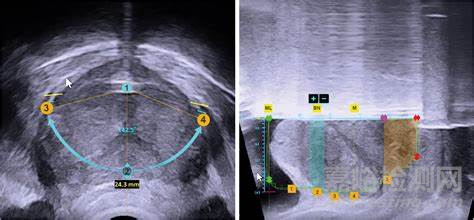

Hydros手術(shù)機(jī)器人是一款為 BPH(良性前列腺增生)提供 Aquablation 療法的 AI 驅(qū)動的平臺。將實(shí)時(shí)超聲成像與膀胱鏡檢查相結(jié)合,為外科醫(yī)生提供整個(gè)前列腺的多維、詳細(xì)的視圖,從而能夠根據(jù)每位患者的獨(dú)特解剖結(jié)構(gòu)制定個(gè)性化的治療計(jì)劃。

圖像引導(dǎo):系統(tǒng)集成了新一代超聲成像、數(shù)字膀胱鏡檢查和雙高清觸摸屏,可增強(qiáng)解剖結(jié)構(gòu)的可視化,并可同時(shí)查看超聲和膀胱鏡檢查圖像。

實(shí)時(shí)、多維成像:結(jié)合了膀胱鏡可視化、超聲成像和規(guī)劃軟件,為外科醫(yī)生提供了治療區(qū)域的多維視圖??蓪?shí)現(xiàn)個(gè)性化治療以及手術(shù)過程中的實(shí)時(shí)監(jiān)控。

個(gè)性化治療計(jì)劃:借助前列腺的多維視圖,外科醫(yī)生會為患者創(chuàng)建具體的治療區(qū)域地圖,指定要切除的區(qū)域,同時(shí)保留控制勃起、射精功能。